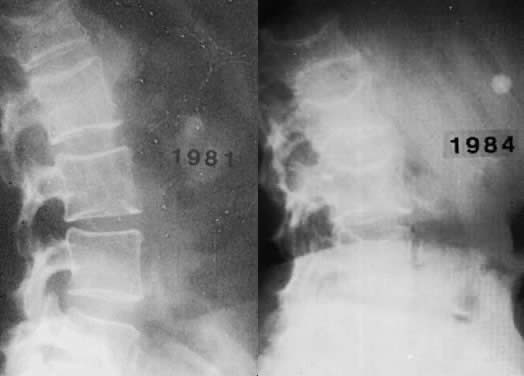

Radiograph of the spine of a patient with postmenopausal (involutional) osteoporosis. A. At 51 years of age. B. At 54 years of age. The patient suffered two hip fractures in the intervening 3 years.